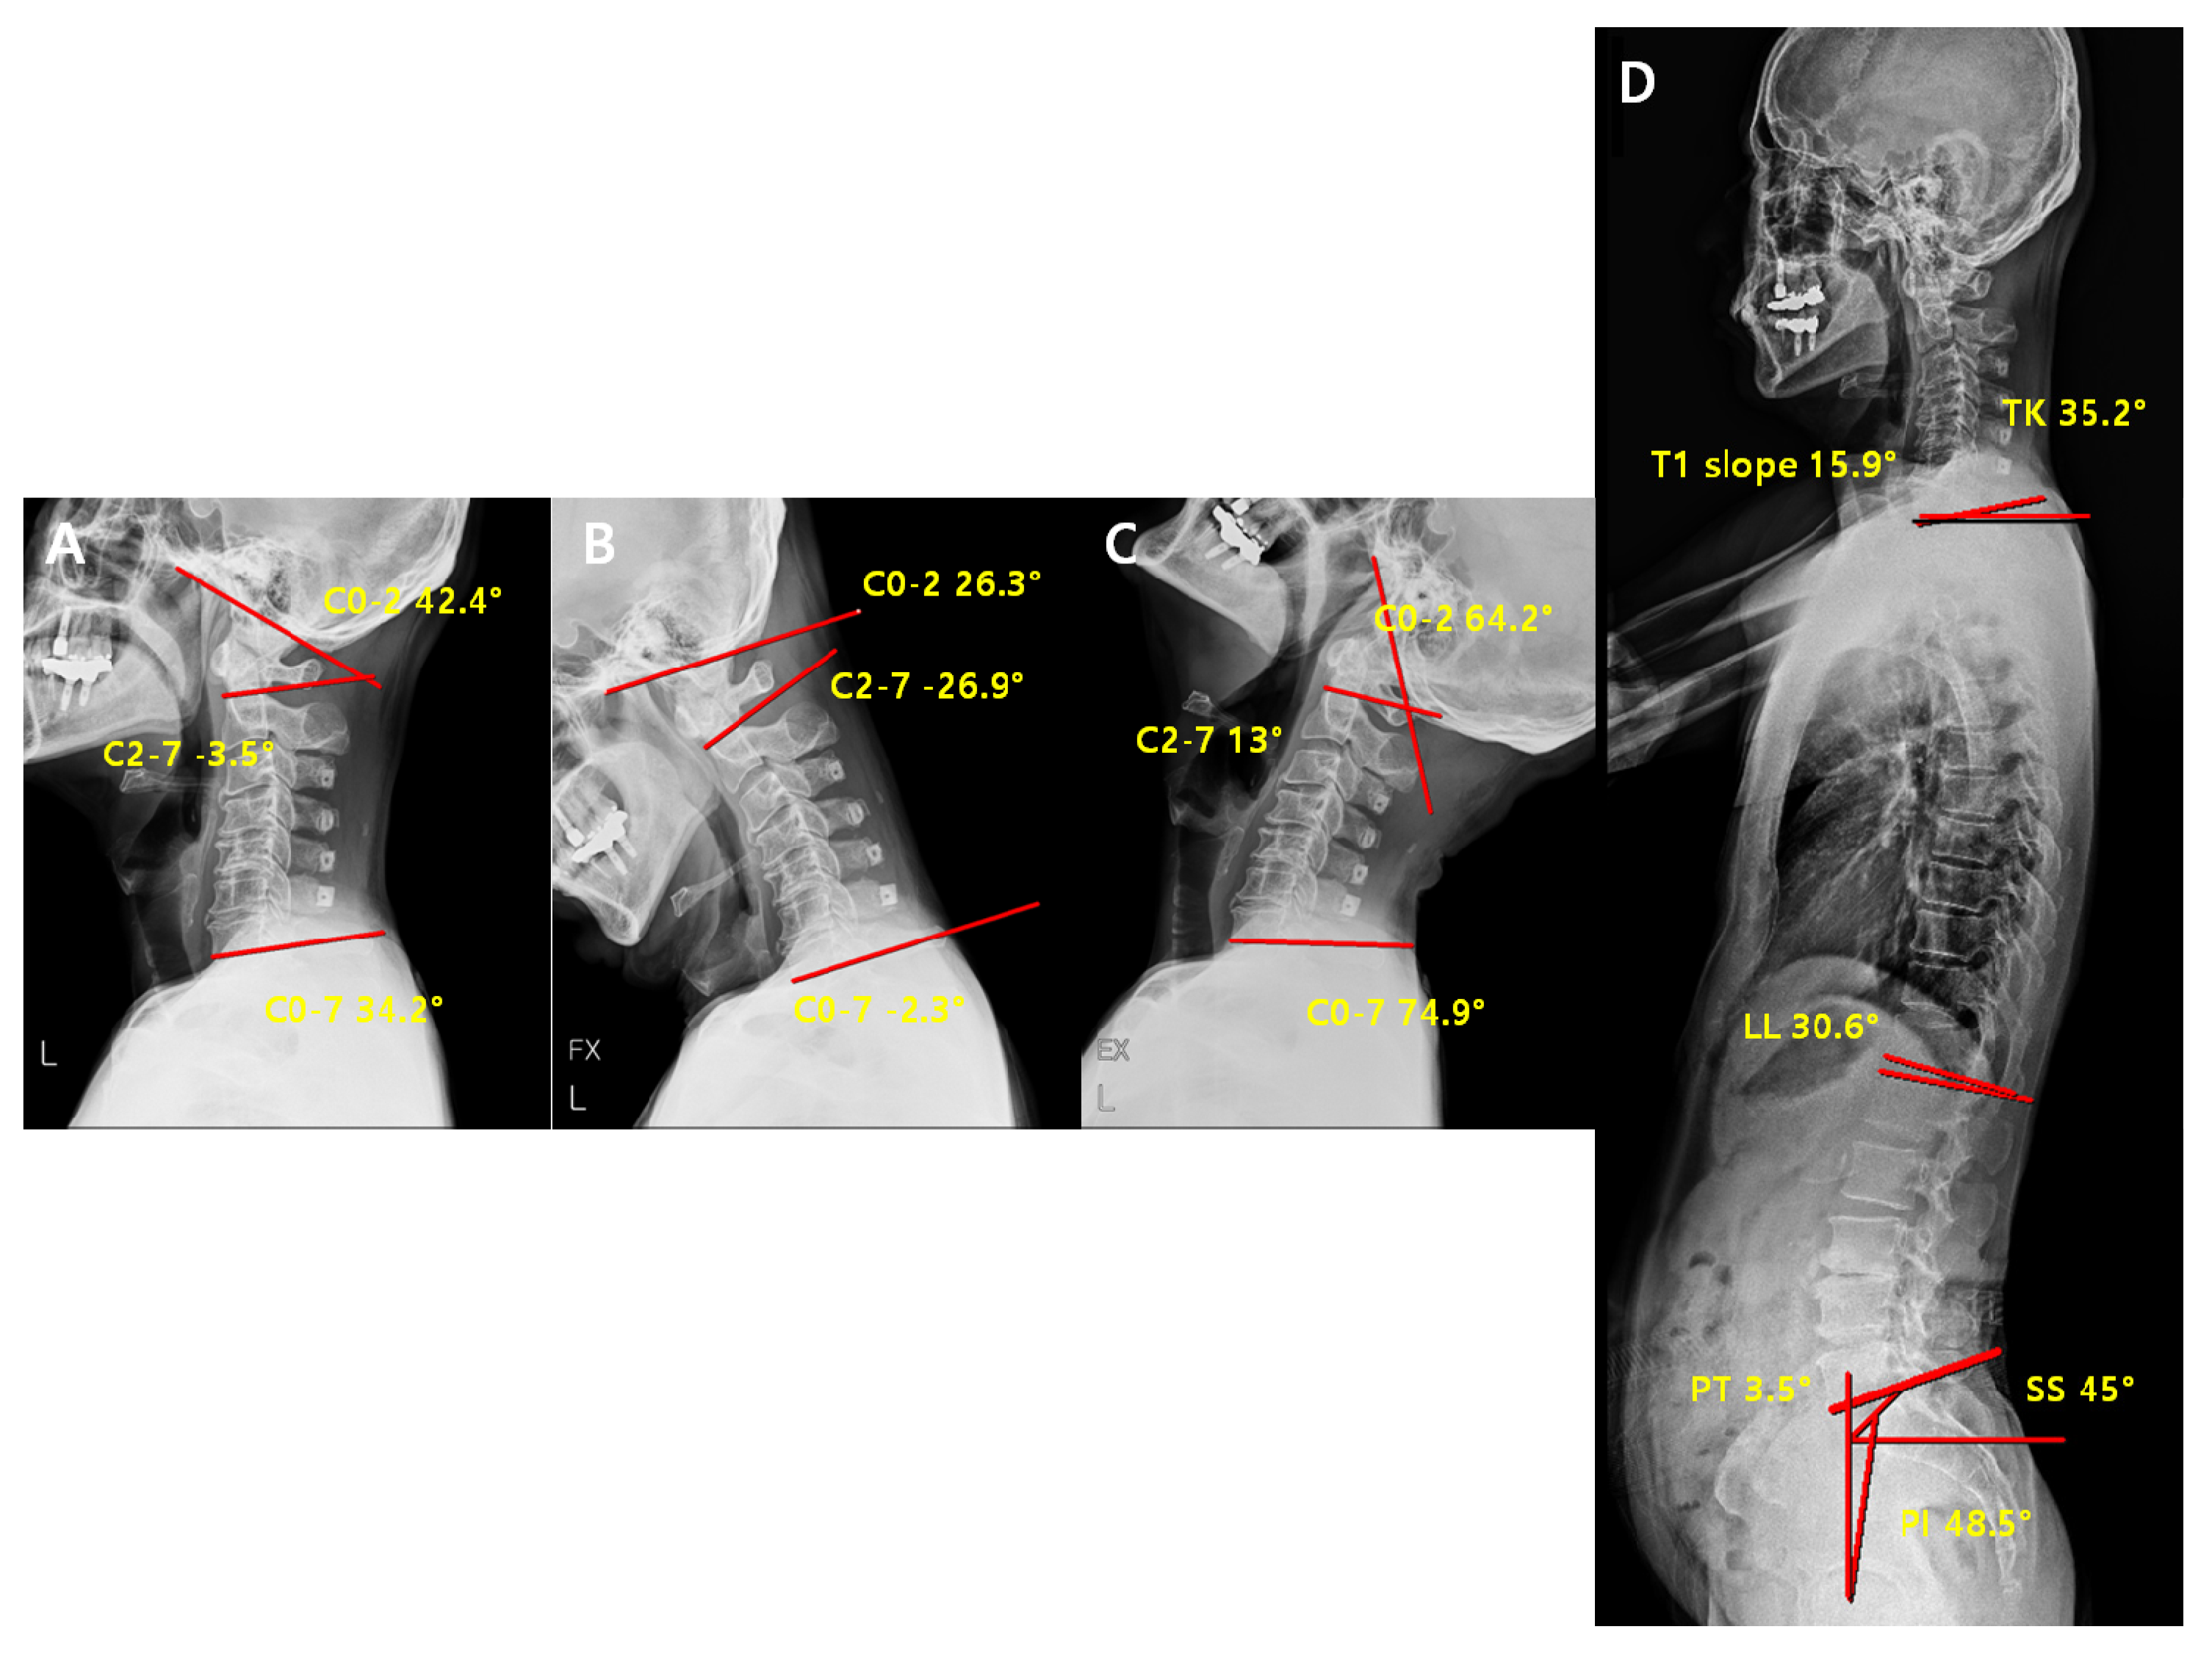

2.3. Radiographic Measurement

| Parameters | Definition |

|---|---|

| C2-7 Cobb angle | The intersection angle between the line perpendicular to the line parallel to the C2 lower endplate and the line perpendicular to the line parallel to the C7 lower endplate |

| C0-2 Cobb angle | The occipito-cervical angle, which is the intersection angle between the McGregor line and the line parallel to the C2 lower endplate and is used to evaluate the curvature of the upper cervical spine |

| C0-7 Cobb angle | The intersection angle between the McGregor line and the line parallel to the C7 lower endplate |

| C0-2/C0-7 | The value of C0-2 Cobb angle divided by C0-7 Cobb angle |

| C2-7/C0-7 | The value of C2-7 Cobb angle divided by C0-7 Cobb angle |

| T1 slope | The intersection angle between the tangent line and the upper plate of the T1 vertebral body |

| SS (Sacral Slope) | The angle formed by a line drawn along the endplate of the sacrum and a horizontal reference line |

| PT (Pelvic Tilt) | The angle formed by a line drawn from the midpoint of the sacral endplate to the center of the bicoxofemoral axis and a vertical and a vertical plumb line |

| PI (Pelvic incidence) | The angle formed by two vectors: (1) The line joining the bicoxo-femoral axis to the center of the sacral end plate and (2) A line perpendicular to the sacral endplate |